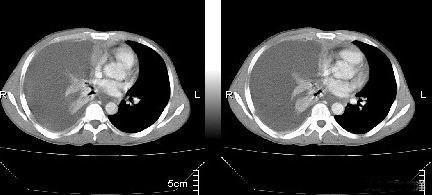

肺癌转移意味着几乎失去治愈机会,治疗的目地是减少症状,改善生活质量,延长生存时间。随着医学的发展,靶向药物和免疫治疗使得许多肺癌转移患者获得了更长的生存期,甚至可以带瘤生存很多年,近期一个女性患者,发现肿瘤时已经是双肺、骨、脑转移,通过靶向治疗后骨转移肿瘤灶已经不再显示有癌细胞活性,脑转移病灶也明显好转,生存预期由原来的六个月延长到至少2年。